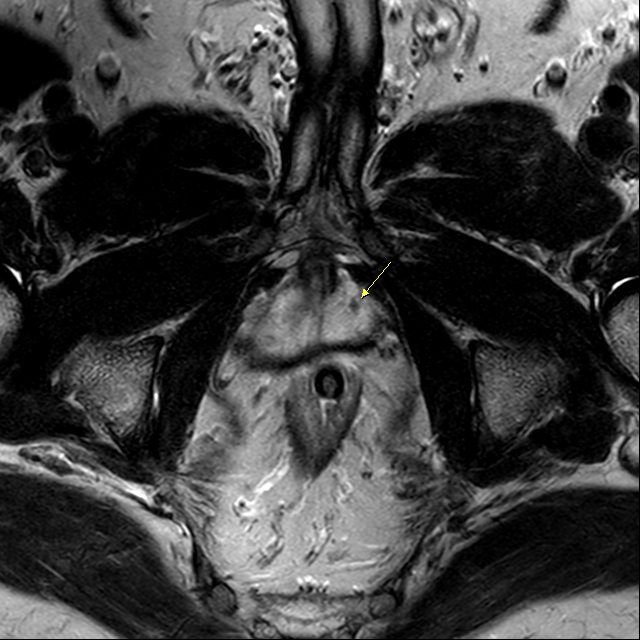

The single greatest breakthrough has been the introduction of multiparametric MRI (mpMRI).

mpMRI provides unparalleled detail by:

> Identifying suspicious lesions

> Measuring water movement within tissue (Diffusion-Weighted Imaging [DWI])

> Assessing blood flow patterns (Dynamic Contrast Enhancement [DCE]).

With mpMRI, doctors can:

> Avoid unnecessary biopsies in around 30% of men > Improve the detection of aggressive cancers

> Perform MRI-guided fusion biopsies for highly accurate sampling of suspicious regions.

This transformative precision diagnostic technique has become well established over the past five years, allowing prostate cancer to be diagnosed and graded more reliably than ever before.